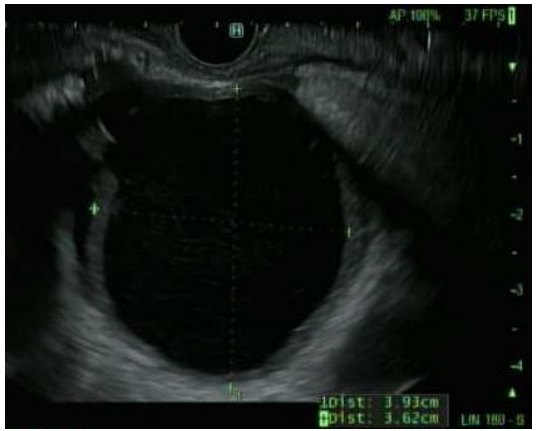

Figure 1. Endoscopic ultrasound (EUS) of the gallbladder. Courtesy of Tony Brar, M.D.